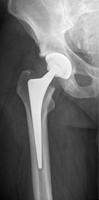

Die Hüftgelenk-Endoprothese wird zementiert oder zementfrei verankert, als Totalendoprothese mit Ersatz der Gelenkpfanne oder für den geriatrischen Patienten als Duokopf-Prothese eingebracht.